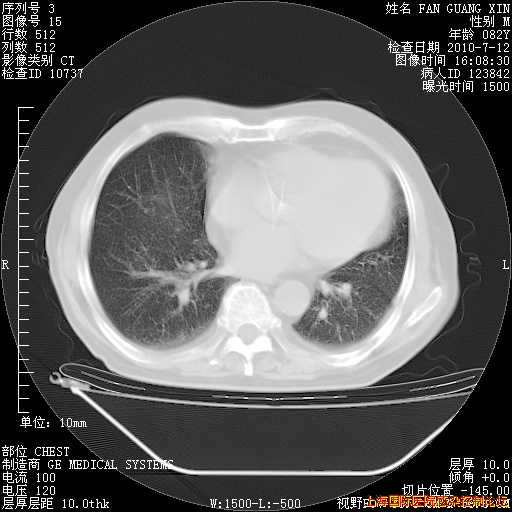

6月12日肺窗

回复

整整相隔30天的肺部CT好像有所好转啊。甲强龙减量第3天,需要观察体温。

海管,自昨日你和我通完话后,不知您岳父消化道症状有无缓解?体温怎样?阅读7.12日胸部ct,个人认为目前激素治疗是有效的,甲强龙减量是适宜的。因在抗痨治疗,需密切观察肝功、肾功能和血常规。不过,老年、长期住院和大量使用激素,很担心菌群失调发生